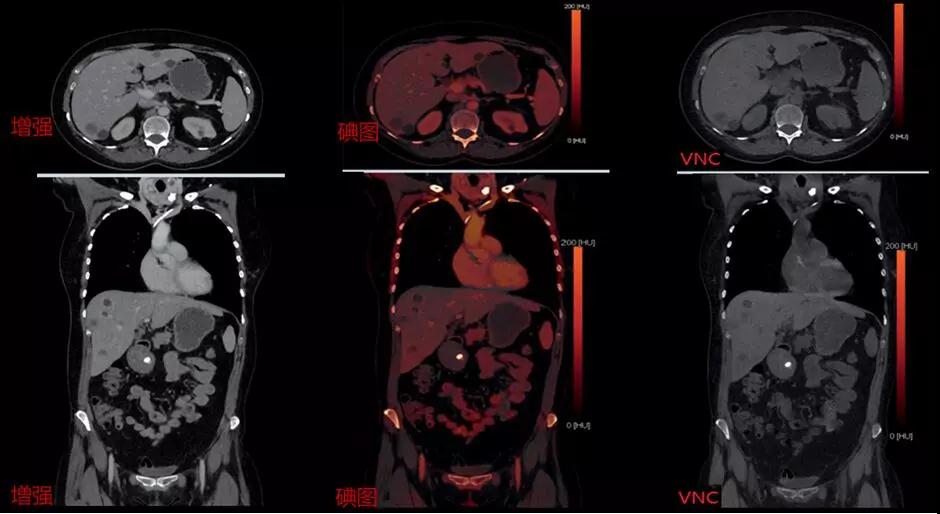

CT發展方向為宏觀的組織形態學診斷到微觀組織成分分析,因此雙能量成像也是各個廠家研發CT的方向之一,西門子獨創采用雙源雙能量成像技術,同時具備4檔電壓組合:70/Sn150、80/Sn150、90/Sn150、100/Sn150可根據掃描部位更合理選擇電壓組合,因此可以做到更精準,更綠色,是業內唯一可用于兒童的雙能量成像。

△高低能譜0重疊,精準分辨和量化物質成分

△雙能量增強掃描可一次性獲得常規增強圖像、碘圖、及VNC